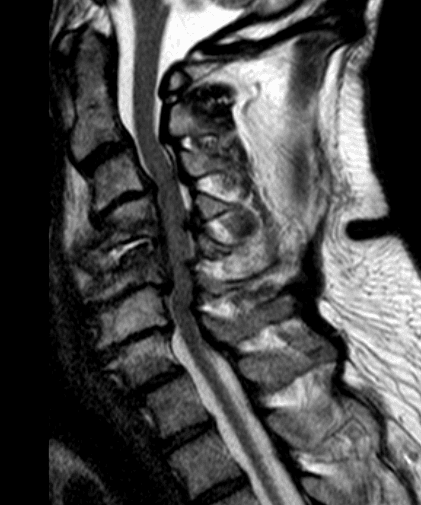

I dati di laboratorio come la conta leucocitaria e il dosaggio di velocità di eritrosedimentazione e proteina C reattiva (alterata nel 95% dei casi di spondilodiscite) possono essere utili indicatori della presenza di infezione. La radiografia tradizionale risulta poco utile nelle fasi iniziali, presentando una sensibilità e specificità rispettivamente dell’82% e 57%. Il gold standard nella diagnosi strumentale della patologia è la Risonanza Magnetica (RM), che permette una diagnosi precoce con una sensibilità e specificità del 92% e 96%. Nel caso di impossibilità ad eseguire una RM, la Tomografia Computerizzata (TC) si rivela una valida opzione diagnostica che permette inoltre di effettuare biopsie TC-guidate utili alla definizione del germe responsabile. La tomografia ad emissione di positroni (PET) rappresenta un utile completamento diagnostico, soprattutto al fine di una corretta diagnosi differenziale.